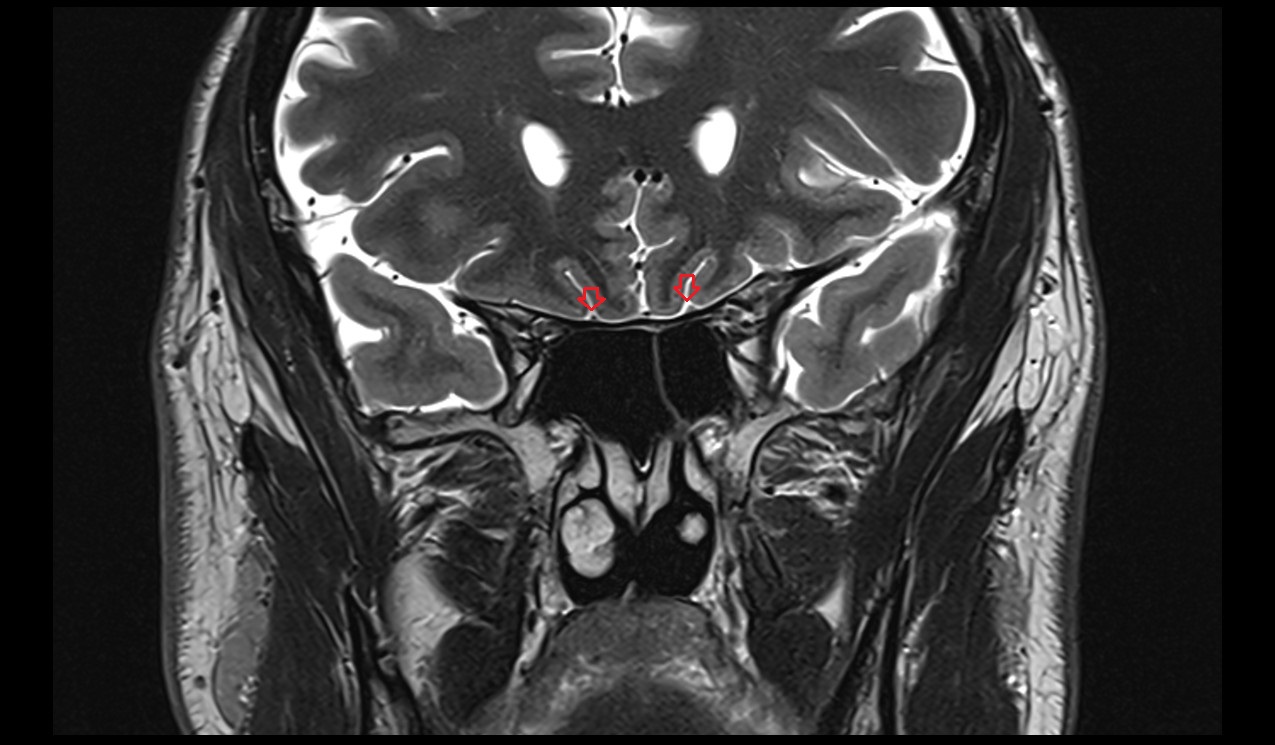

- Pituitary stalk